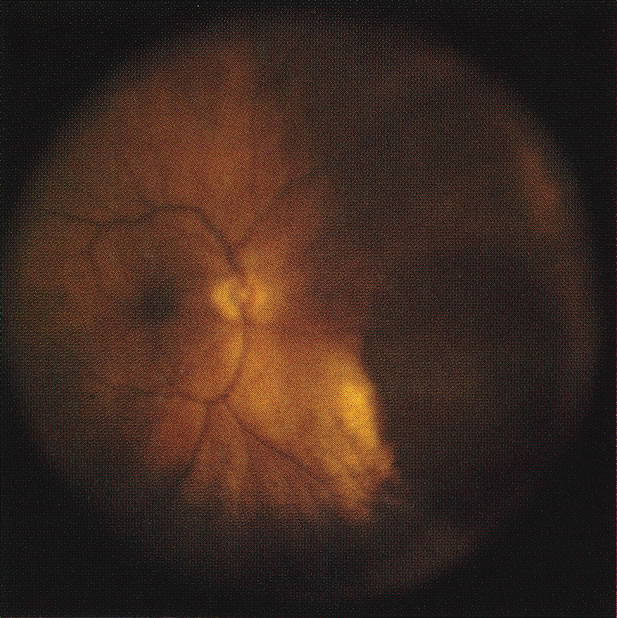

Necrotic melanomas account for approximately 5% of uveal melanomas; in the majority of cases, there is intraocular inflammation accompanying the cataract.7–9Figures 1 and 2 demonstrate a typical case. The patient had a long history of unilateral decreased vision. The eye had become painful 1 month before admission, and he was referred for evaluation of uveitis. Clinically, there was a dense, unilateral cataract with significant intraocular inflammation, which was manifested as a ciliary flush with 2+ cells and flare. Media opacity obscured all fundus detail. An immersion B-scan demonstrated a large intraocular tumor that was most consistent with a uveal melanoma. The eye was removed, and the diagnosis was confirmed histologically.10

Unfortunately, imaging studies are not always diagnostic. The A- and B-scans shown in Figures 3 and 4 were from a patient with unilateral media opacity referred for evaluation and treatment of a presumed uveal melanoma. Occasionally, if the cataractous lens is scanned tangentially, artifact can occur. A repeat ultrasound at our institution was negative for tumor, and the referral ophthalmologist who performed a cataract extraction noted that no tumor was present and that the patient has an excellent visual outcome. In contrast, the patient shown in Figure 5 was referred with a presumed uveal melanoma with secondary inflammation and a history similar to that described for the patient shown in Figure 111 Ultrasound and CT examinations were not diagnostic. Because the eye was blind and painful, it was enucleated, and an extremely necrotic uveal melanoma was noted histologically. In some necrotic melanomas, the fundus cannot be visualized and the diagnosis cannot be established with imaging studies. Very rarely, a necrotic uveal melanoma can produce sufficient pigment dispersion into the vitreous to obscure the correct diagnosis.12